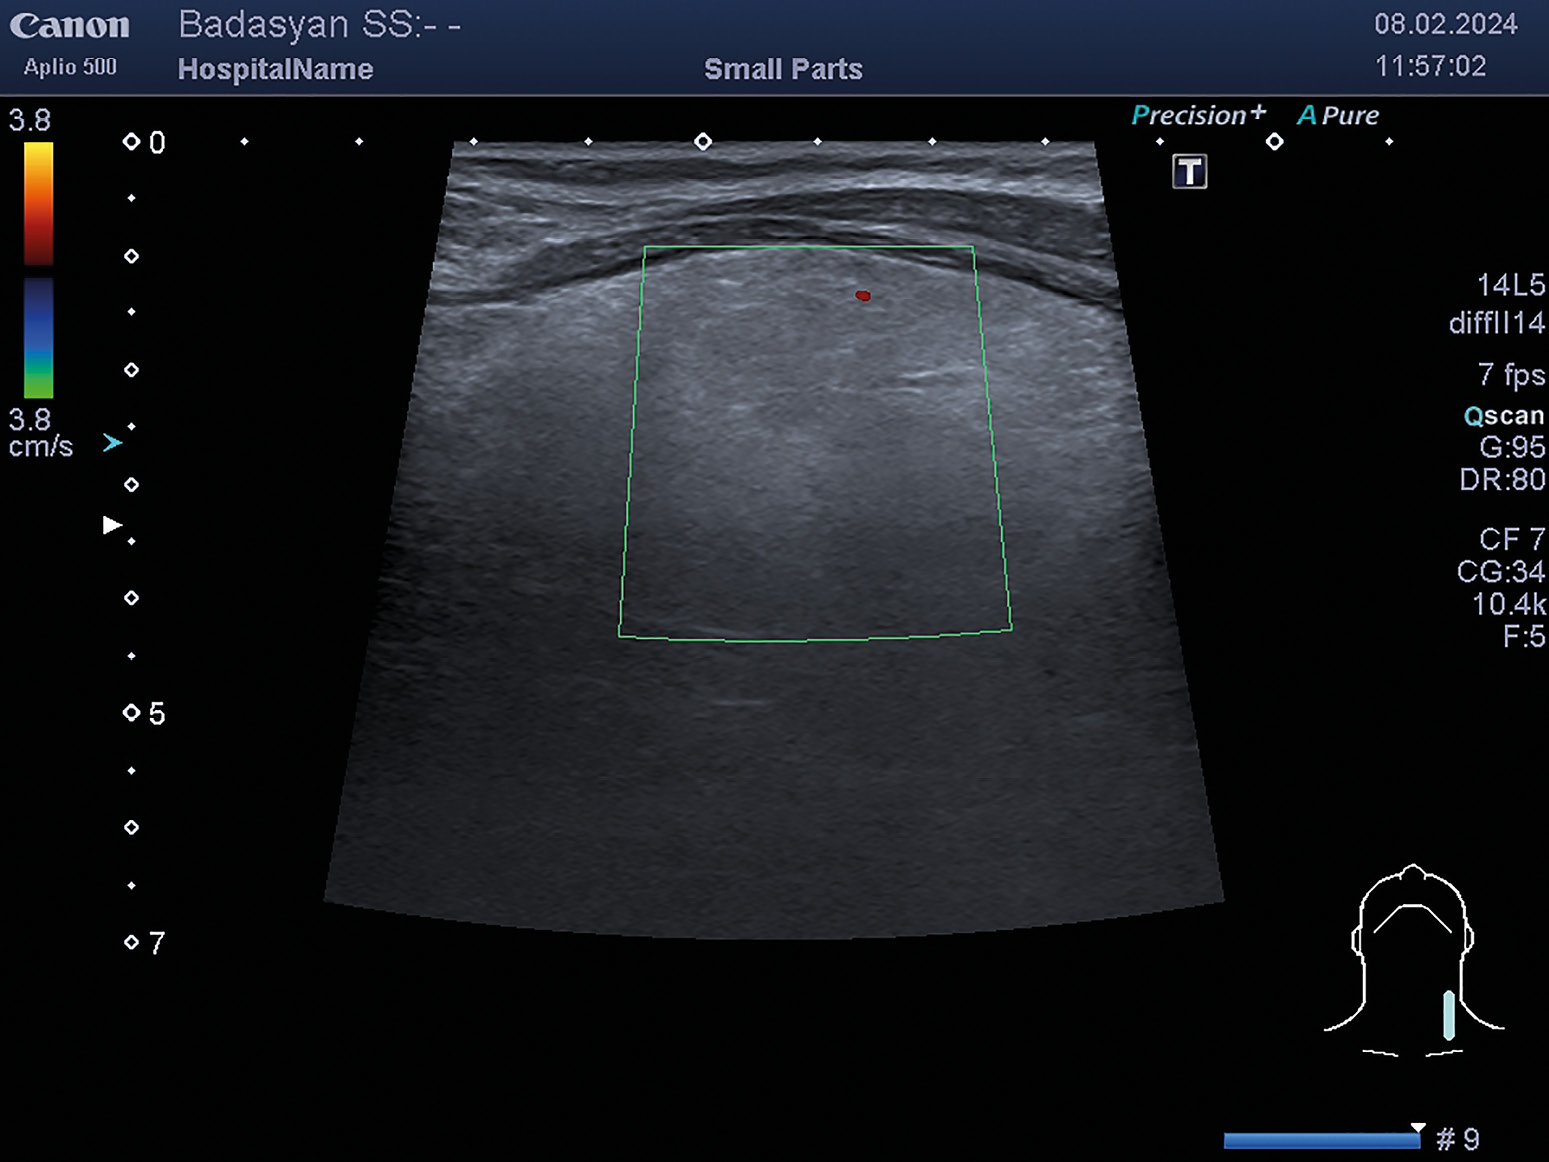

2. Рисунок 2. Цветное допплеровское картирование щитовидной железы.

Тема

Тип Исследовательские инструменты

Посмотреть (189KB)

Метаданные ▾